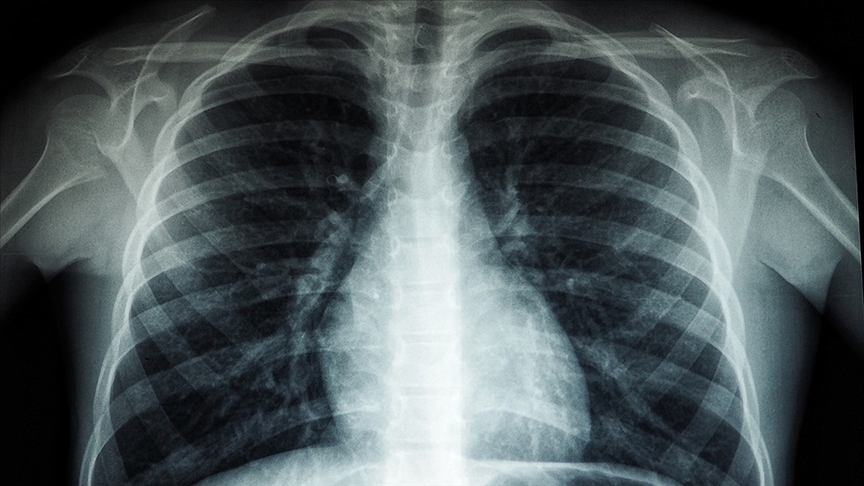

PM2.5 olarak adlandırılan ince partiküller, mikrometre boyutları nedeniyle akciğerlerin en derin bölgelerine kadar ulaşabiliyor. Uzmanlara göre bu parçacıklar; astım, kronik solunum hastalıkları ve akciğer kanseriyle ilişkilendiriliyor. Düşük seviyelerde bile hücresel düzeyde ciddi hasara yol açabiliyorlar.